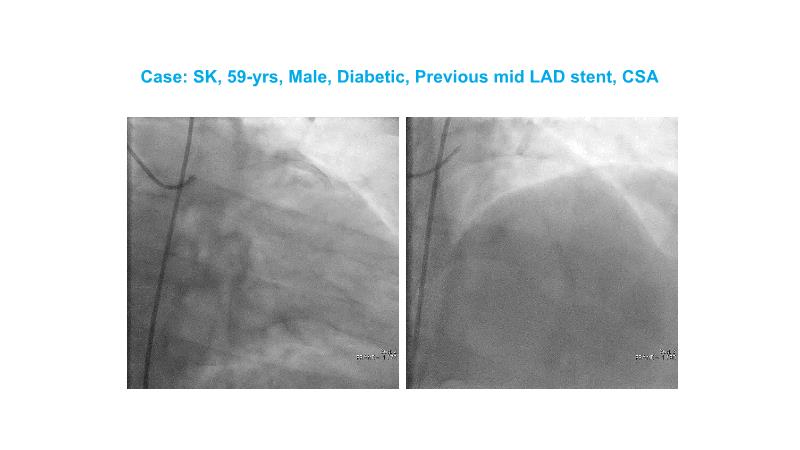

Over the last five years, we have learned that there is a new tool for treating calcium, the greatest enemy of interventional cardiology, which can take various forms: intravascular lithotripsy. In this session, look at how to master this technique in different scenarios, from eccentric calcified lesions to left main bifurcations.